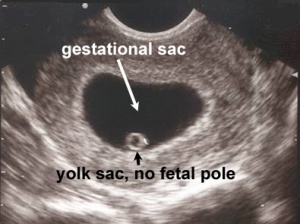

File:fetal_pole.jpg|Fetal pole (Thickening of yolk sac on one side) | |||

- 6-7 weeks

- Fetal Pole

- First visual manifestation of fetus (or "embryo")

- Thickening of margin on yolk sac

- Fetal Pole

- Cardiac activity present (FHR ~100-115 bpm)

- Crown rump length: ~5mm

- Gestational sac >10mm without visible yolk sac

- Gestational sac >18mm without fetal pole